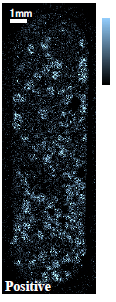

カプセル剤タイプ薬の断面についてTOF-SIMSによる質量イメージング分析を行いました。断面加工を行い、薬剤全体(約7mm×20mm)とその内部の顆粒一粒(約500μmΦ)に着目したイメージング事例をご紹介します。

光学顕微鏡像とTOF-SIMSイメージング

| 光学顕微鏡 | ●成分A | ■成分B | ▼成分C | |

●成分A:イブプロフェン

■成分B:デキストロメトルファン臭化水素酸塩水和物

▼成分C:無水カフェイン